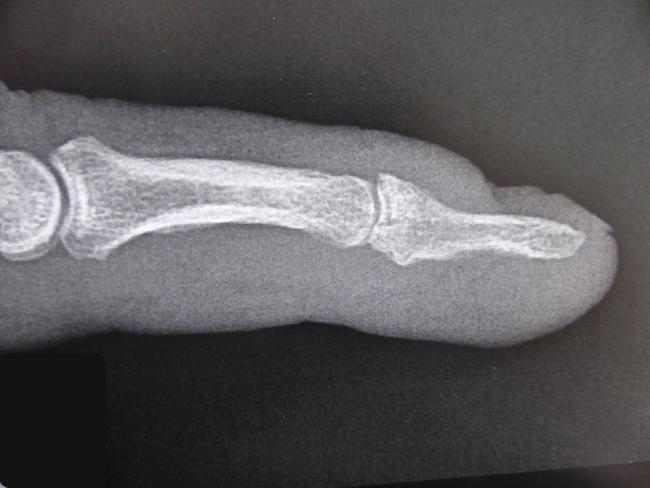

Des radiographies du doigt de face et de profil sont indispensables pour rechercher un arrachement osseux de l’insertion du tendon.

Oui, une réparation chirurgicale est justifiée lorsque le tendon s’est arraché en emportant un gros fragment osseux à la base de la deuxième phalange. Ce gros fragment comporte une surface articulaire qu’il faut parfois remettre en place et fixer chirurgicalement.

Dans ce cas, le tendon a arraché son insertion osseuse. Les surfaces articulaires ne sont plus en face l’une de l’autre.